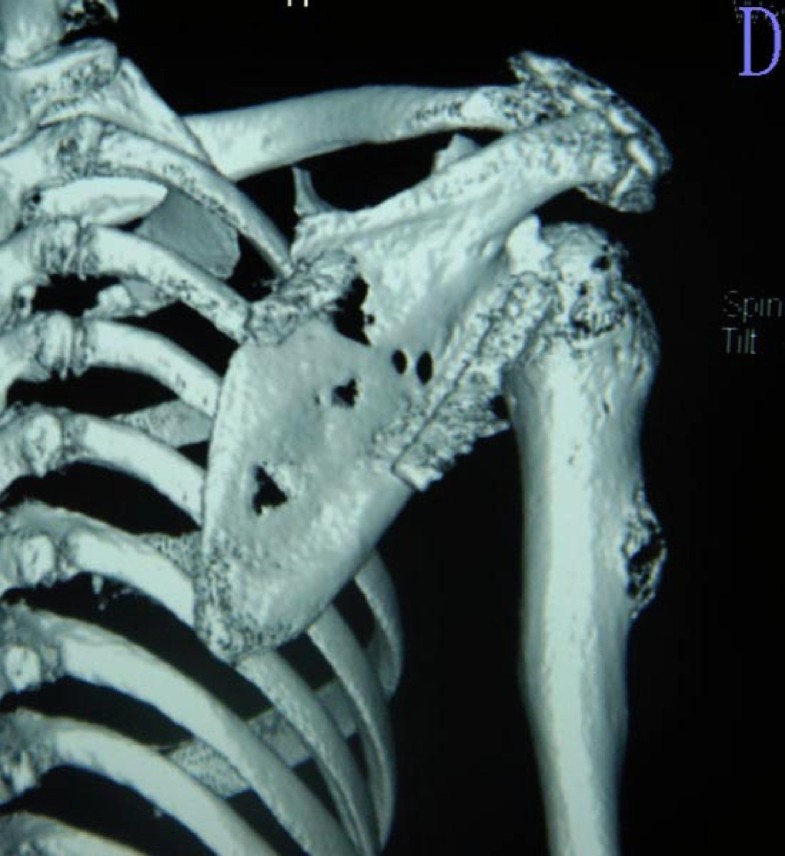

From jeccr.biomedcentral.com

Surgical technique and clinical results for scapular allograft Scapula Bone Cancer neoplasms of the s2 region include those that commonly develop at the ends of the bone (i.e.,. chondrosarcoma is a malignant mesenchymal tumor originating from cartilage. Risk for malignancy increased with age (or 1.09,. tumors occurred most frequently in the body of the scapula. a wide variety of benign and malignant tumors may occur in the. Scapula Bone Cancer.